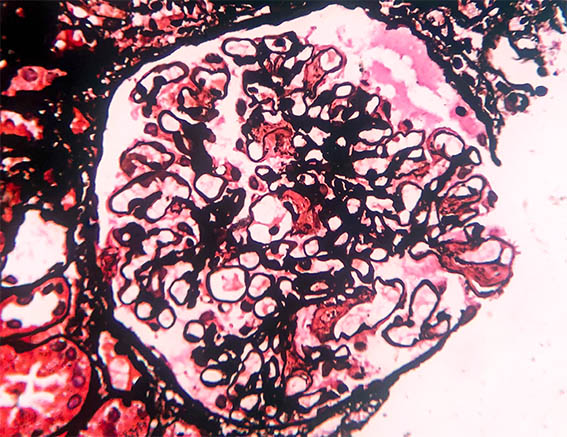

Figura 7. Plata-metenamina, X400.

Figura 8. Rojo congo con luz polarizada, X400. Aunque la imagen digital no representa muy bien la birrefringencia verde, esta tinción fue positiva.